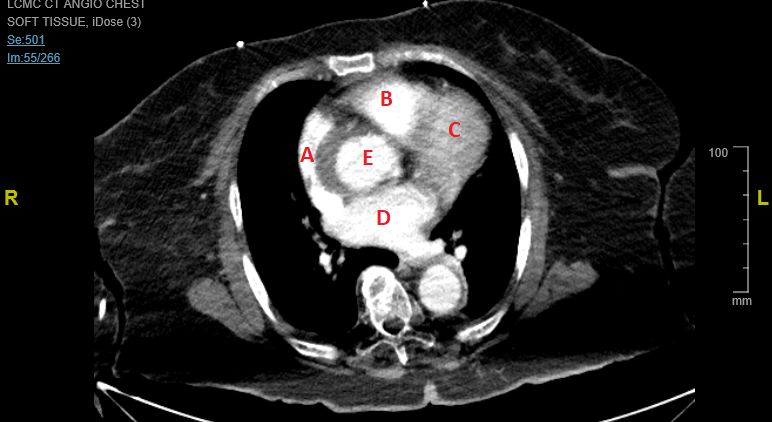

Regarding pericardial effusion, look at the CT. Identify the anatomy. Tell me what you see. What does pericardial effusion look like on that modality?

Yeah...see a flap on the ascending long axis there. E= Ao B= RV C=LV D= LA A =RA.....but I think I see your point...almost looks like the right sided compression is coming from the hematoma? At least impeding RV filling, anyway...